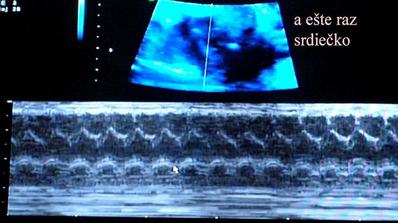

@monika0001 juj dufam ze ste v poriadku takze poradna jooj zasa si popozeras to nadherne srdiecko ze 🙂 ja viem je to nadhera fakt 🙂

@l123456 - tomu ver. asi ani spať nebudem 😀